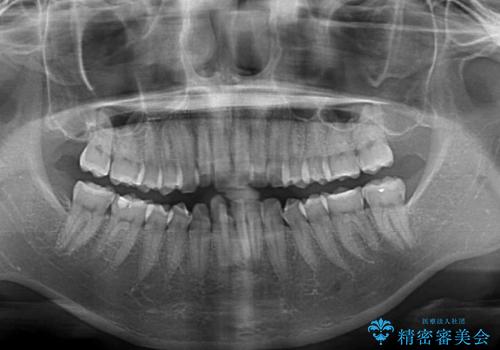

- 上の前歯の出っ歯とでこぼこの歯並びを気にして来院された患者様です。

口元を積極的に引っ込めるために、上下左右の小臼歯4本を抜歯することとしました。

4本の歯を抜歯したことで、飛び出していた口元が引っ込み、横顔が大きく改善されました。

咬み合わせが悪化することのないようにスペースを閉じていくことができ、比較的スムーズに治療を進めることができました。